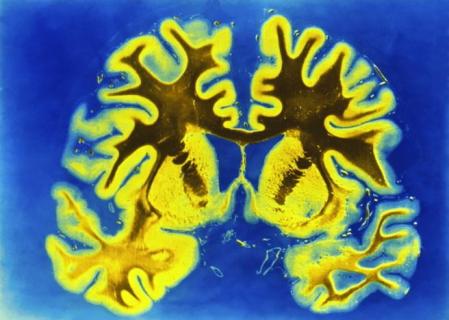

El volumen de materia gris aumenta gracias a la meditación

Esto pudo comprobarse al ver que el volumen de materia gris en el cerebro de personas que llevaban una media de 20 años meditando era mayor que en aquellos que no.